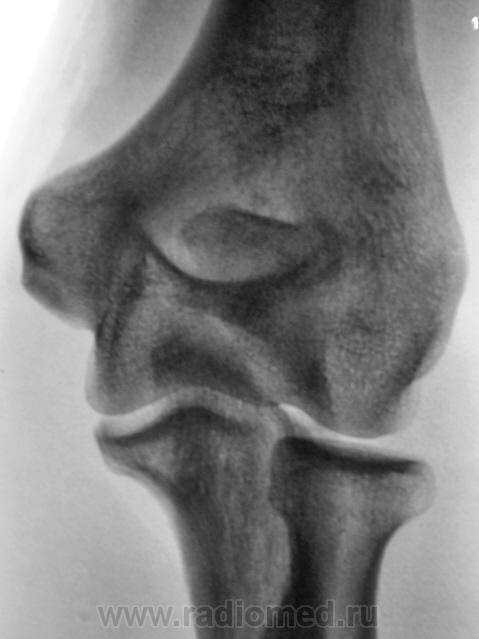

Травма.     Пациент направлен на рентгенографию локтевого сустава.

Перелом локтевого отростка - на операцию

Если рассуждать с точки зрения только диагностики перелома - нет, так как перелом хорошо виден и на стандартных проекциях. С точки зрения дальнейшей лечебной тактики - да. Так как косые проекции выявили безусловную необходимость оперативного лечения.